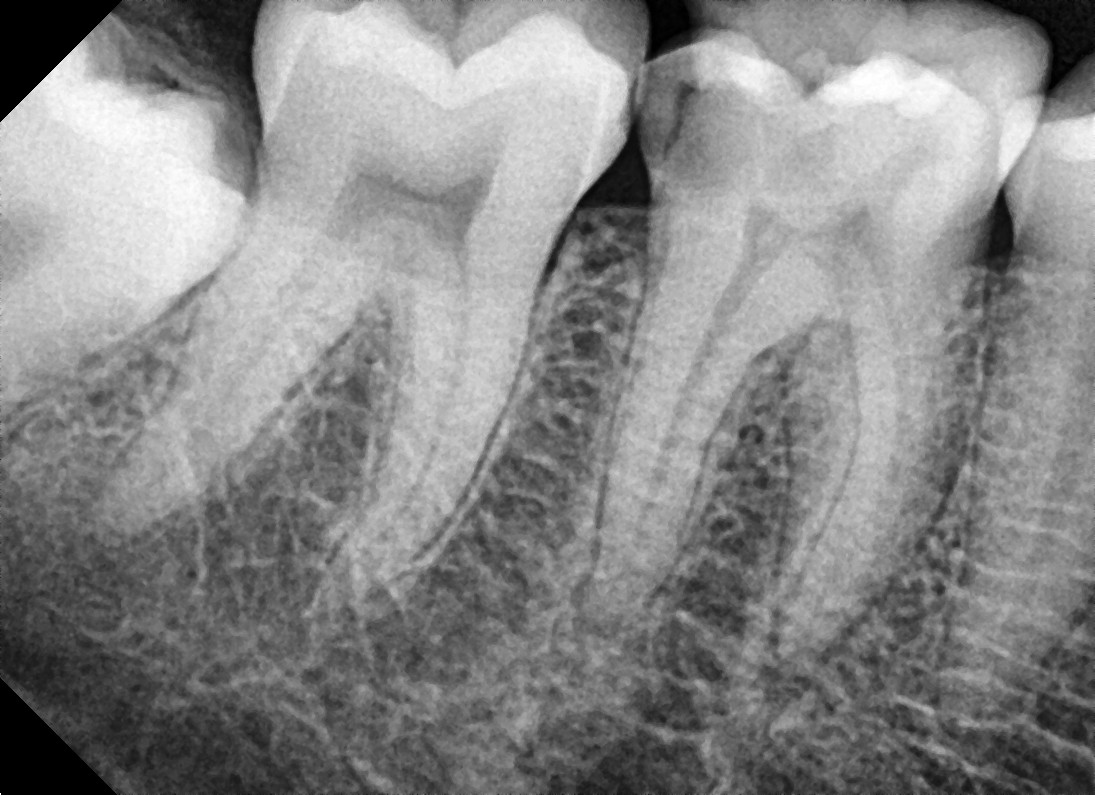

• A diagnosis is made for the tooth with percussion, palpation and cold tests and an x-ray.

• Measurements of the length of the root canal is noted and take x-rays to confirm the length. Ensuring that the entire length of the root canal is cleaned.